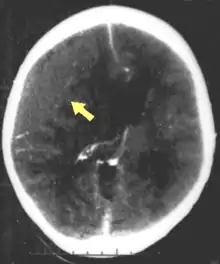

| CT scan showing cerebral contusions, hemorrhage within the hemispheres, and subdural hematoma. There is also displaced skull fracture of left transverse parietal and temporal bones.[2] | |